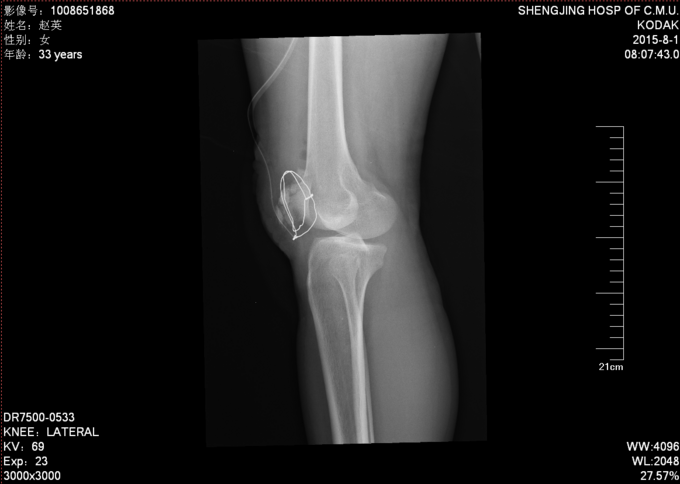

右髌骨开放性骨折 患者急诊行清创缝合后,入院检查后,患者病情平稳,创口1至2天定期换药,观察患者创口愈合,患肢抬高,给予消炎消肿等对症治疗后。入院约一周后创口处无红肿,无渗出,全麻下行右髌骨开放性骨折切口复位张力带内固定术。